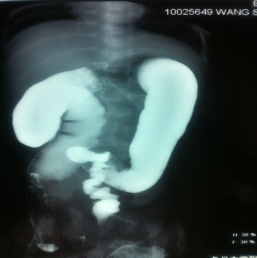

▷ 钡剂灌肠(Barium Enema)

- 无神经节细胞段与近端结肠口径差别、扩张段、狭窄段及移行段改变

- 结肠炎时粘膜锯齿状改变

- 24小时后钡剂滞留

操作简单,方法普及

新生儿确诊率80%

短段型不易诊断